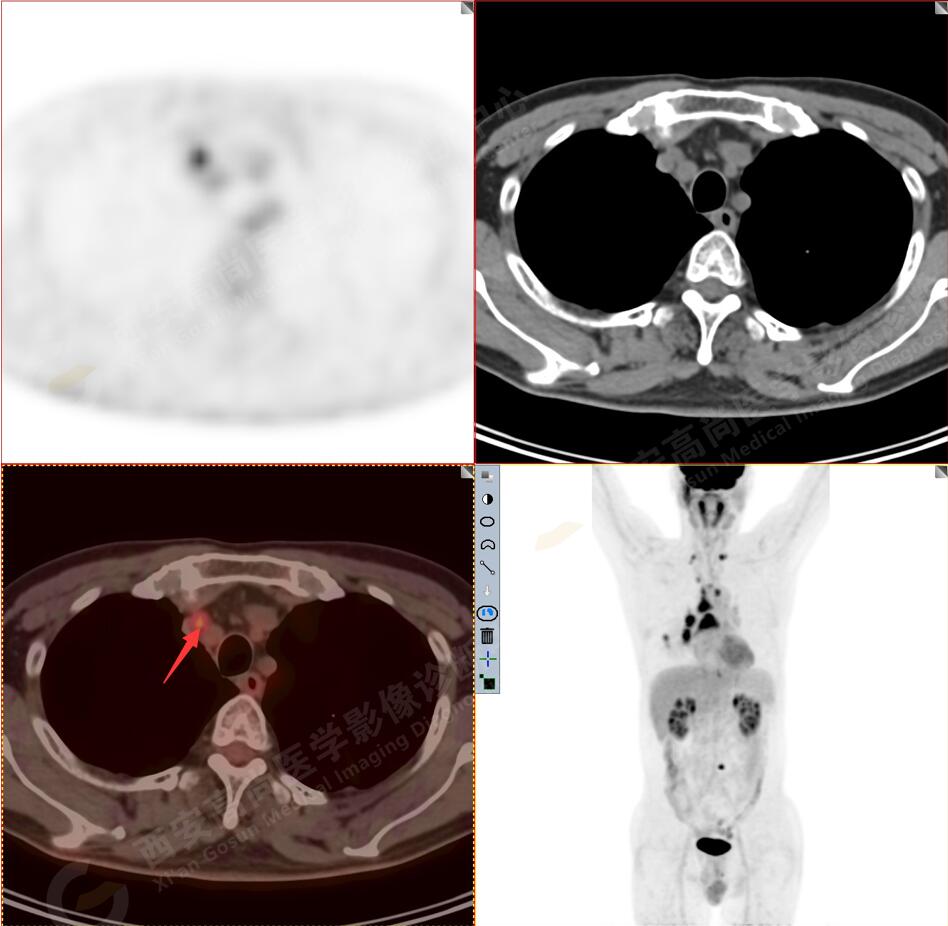

1.以下為肺內原發(fā)灶

1.右肺下葉后基底段軟組織結節(jié)(約1.5cm×1.2cm),與相鄰后胸膜分界不清,呈FDG代謝異常增高,結合病理,符合肺腺癌伴鄰近胸膜侵犯。